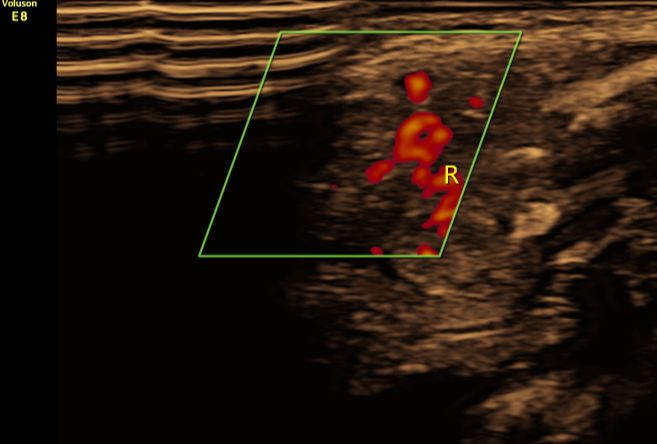

(图4:彩色多普勒超声显示锁骨骨折周围血肿内血流信号较丰富)

②合并周围软组织损伤:骨折周围可见血肿声像,呈不均质低回声。早期新鲜血肿时内部血流信号较丰富,晚期血流信号减少或消失;